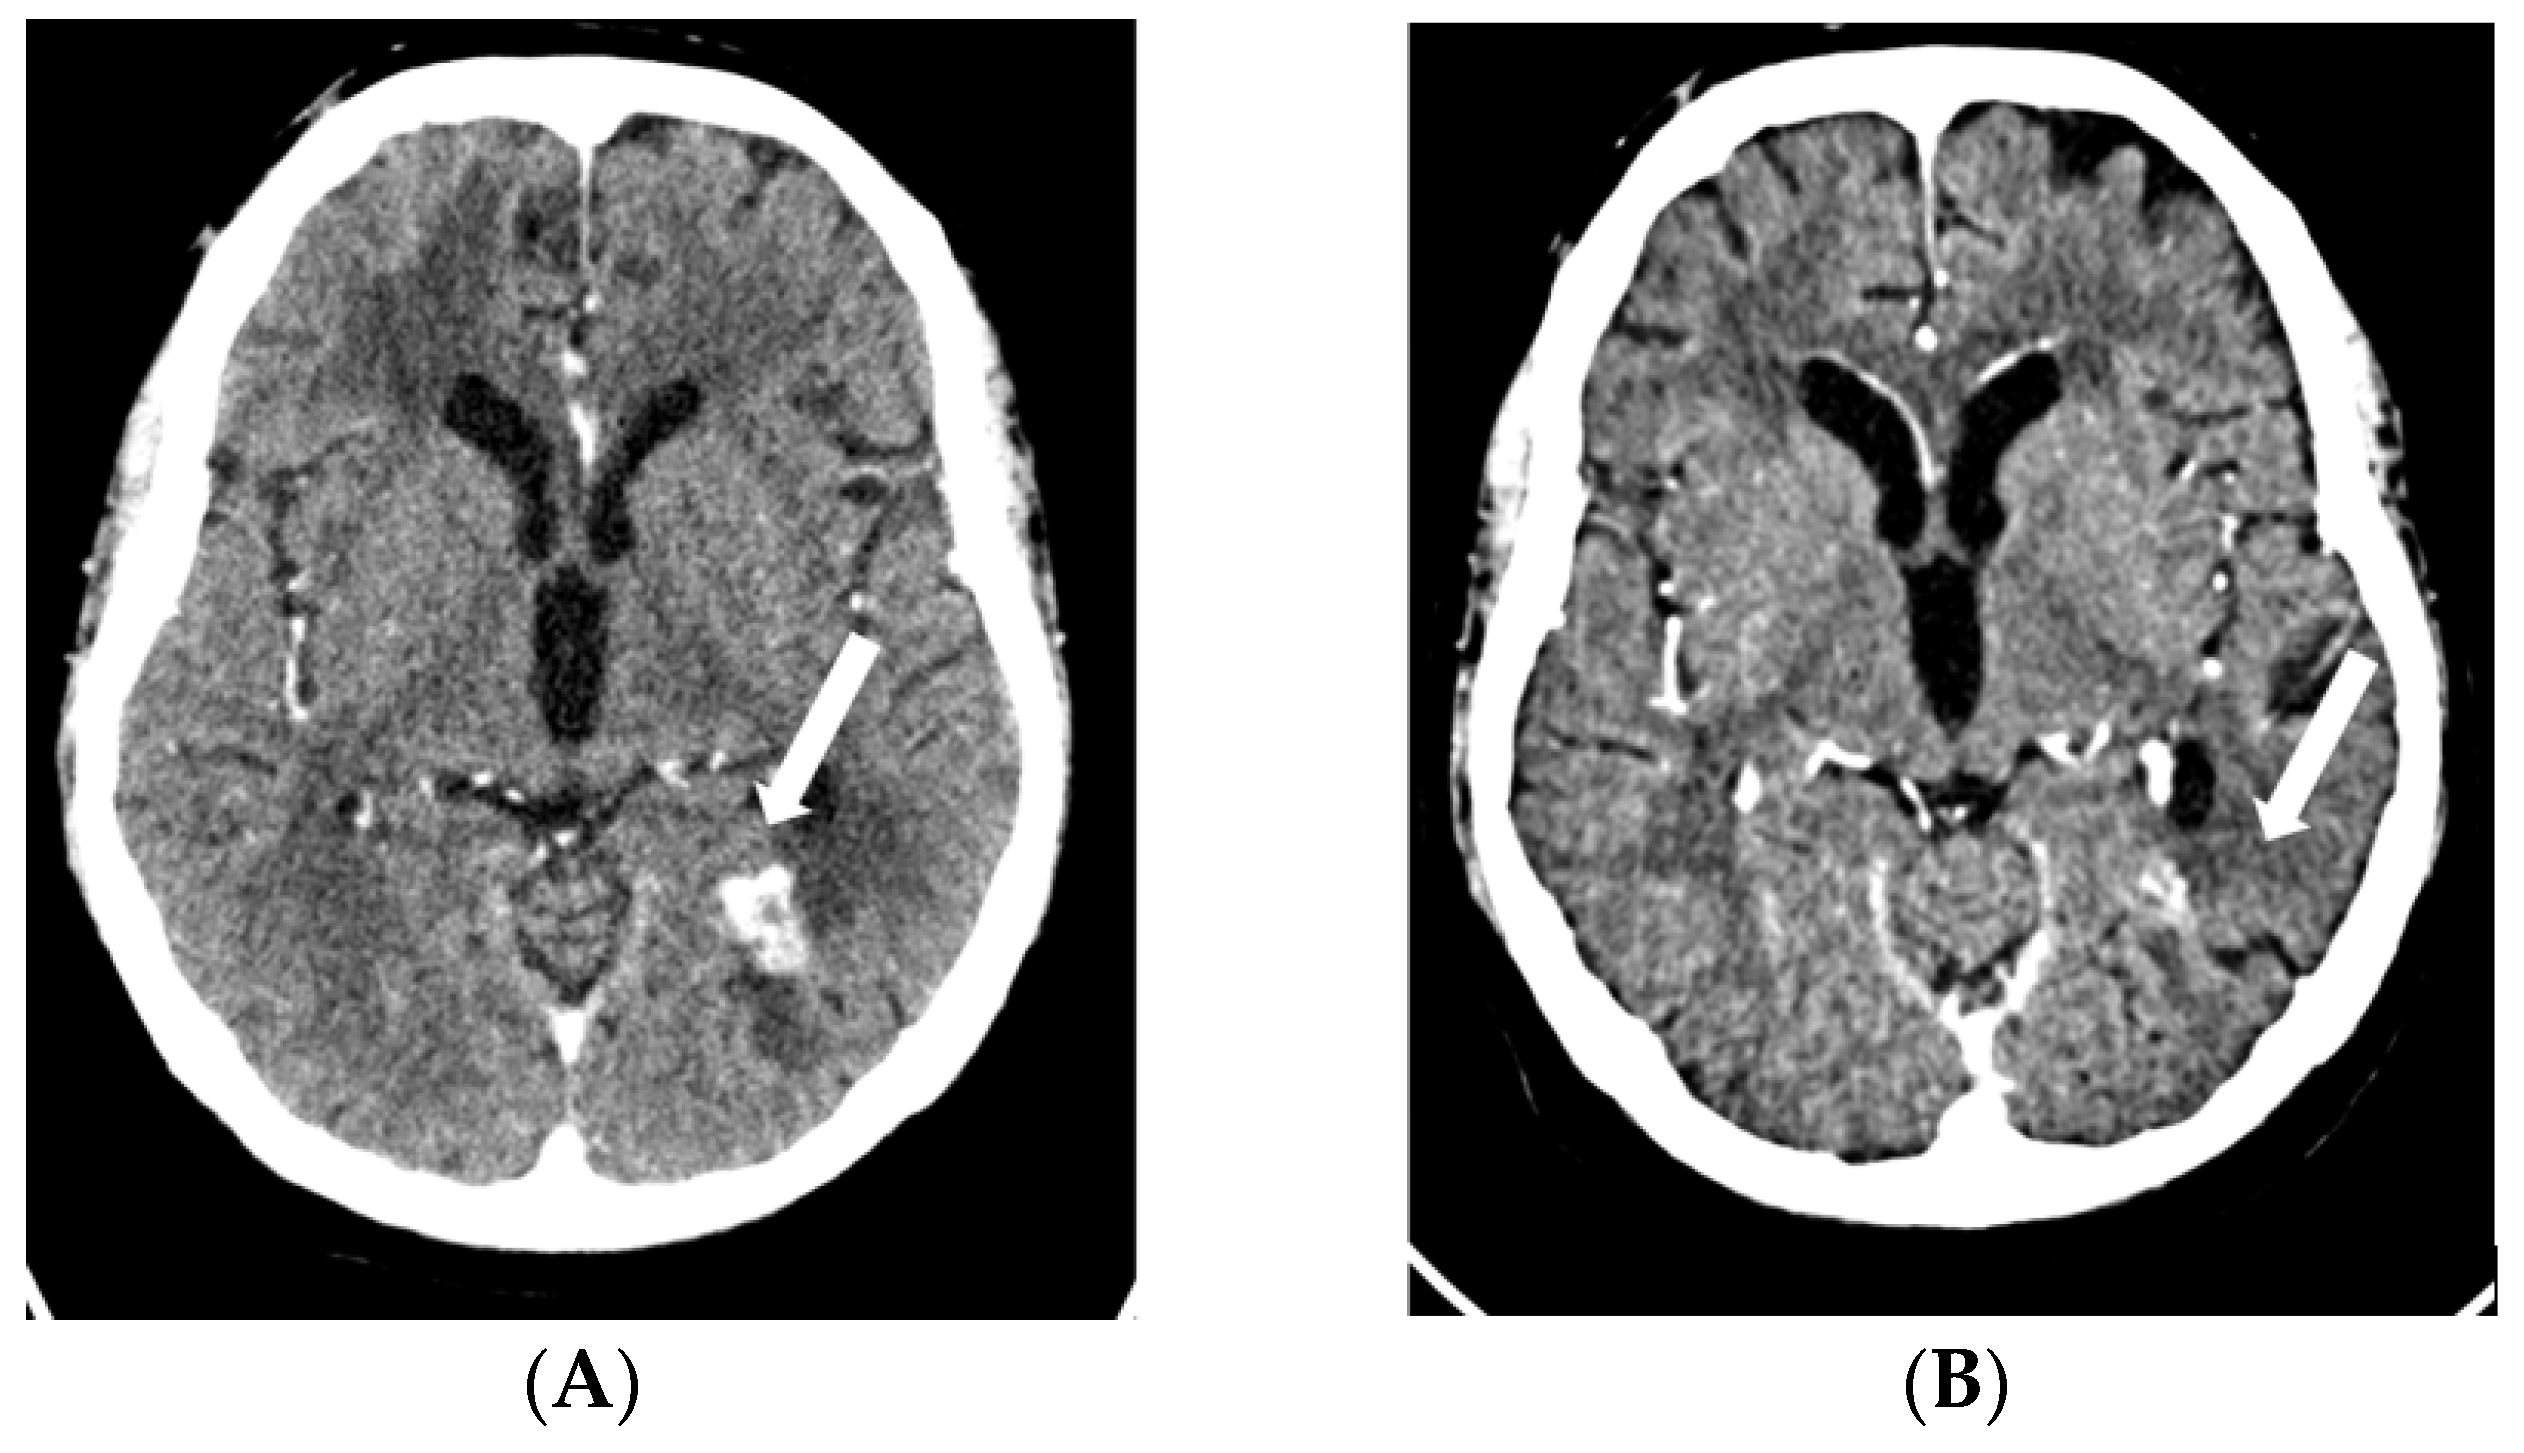

2.1. Case 1

2.2. Case 2

2.3. Case 3